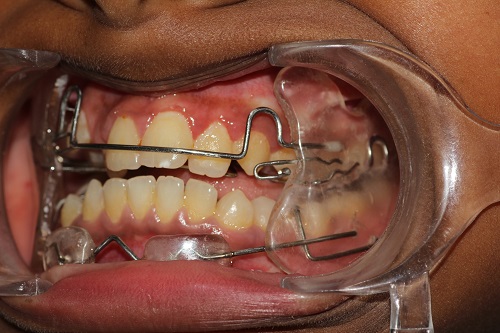

The various treatment offered in the department includes fixed orthodontic treatment with metal, ceramic,self-ligating brackets, treatment with mini-implants, Rapid Maxillary Expansion appliances, orthognathic surgeries to correct facial deformities, distraction osteogenesis procedures with Internal and External distractors, treatment of cleft lip and palate, Pre-surgical Naso Alveolar Moulding on cleft cases, Fixed functional treatment with Forsus, Powerscope, Herbst etc, Lingual Orthodontic treatment, Myofunctional Appliance Therapy, Aligner Orthodontic Treatment ,Myofunctional trainers, Splints- For Temporomandibular joint disorders as well as Class III correctors in growing individuals with appliances such as Tandem Traction Bow Appliance.